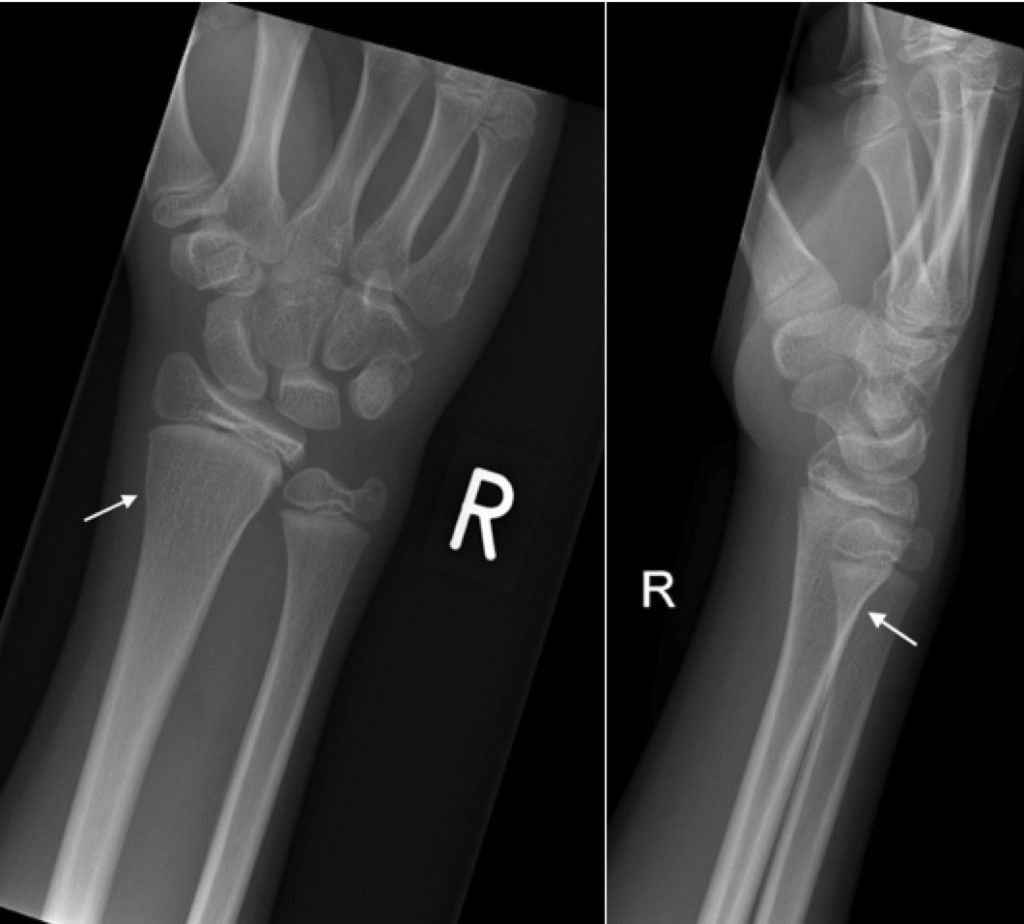

A male patient, aged 32 years old, sustained a left wrist fracture from …

Triquetral fracture. (a) PA radiograph of the right wrist demonstrates …

Example of non-angulated wrist fracture. Initial imaging A and follow …